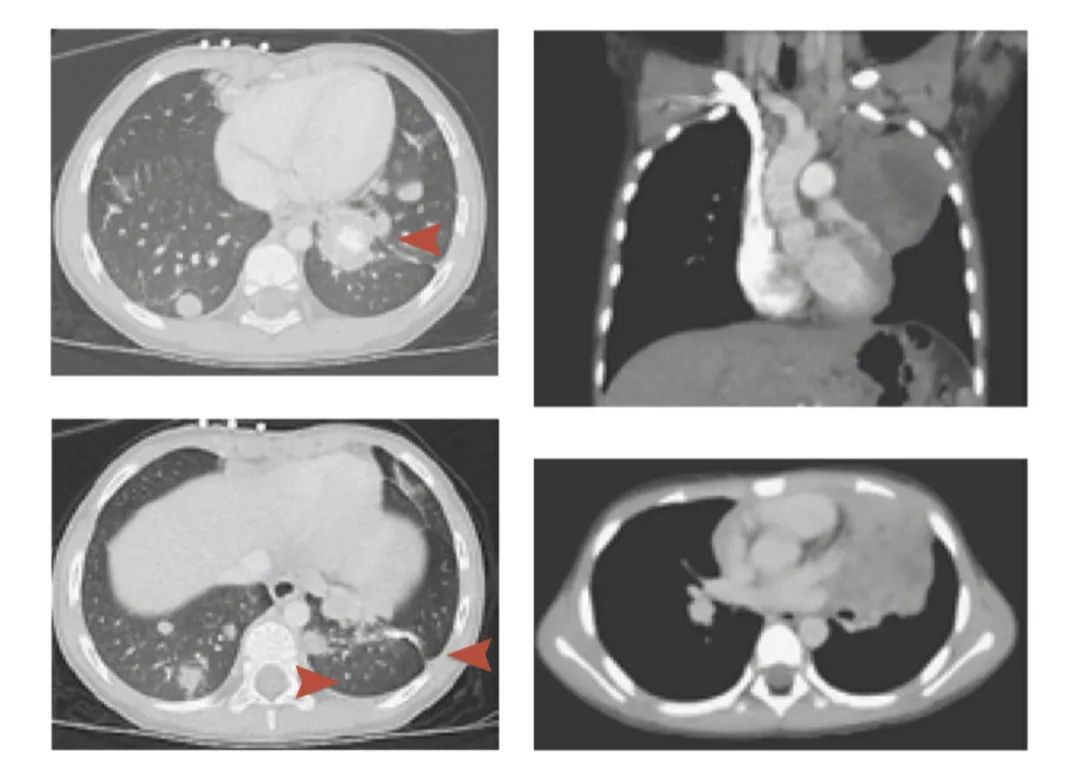

第一例案例中,在男婴出生前7个月,婴儿的母亲曾筛查过宫颈癌,结果为阴性。但在婴儿得到癌症诊断、母亲再次检测宫颈癌时,结果则为宫颈鳞状细胞癌阳性。婴儿在23月大时出现了持续2周的咳嗽症状。胸部计算机断层扫描(CT)显示,婴儿左右肺的气管中出现了几个阴影团。在发现异样后,医生立刻对婴儿进行了肺部活组织检查,并在肺部组织中发现了 神经内分泌癌 (neuroendocrine carcinoma)。

第二例案例中的病人则是一名男孩,男孩的母亲在生育时曾筛查出宫颈息肉,但该肿瘤呈良性,医生评估其转移风险不大,因此允许婴儿正常出生。男孩在6岁时因胸部疼痛而入院检查。医生在检查时,发现男孩的左肺中存在阴影。进一步分析表明男孩患有 肺部黏液腺癌 (mucinous adenocarcinoma)。

左、右2列分别为病例1和病例2中的胸部成像。左列图中红色箭头标示了病例1肺部的癌细胞群。图片来源:Arakawa et al., NJEM